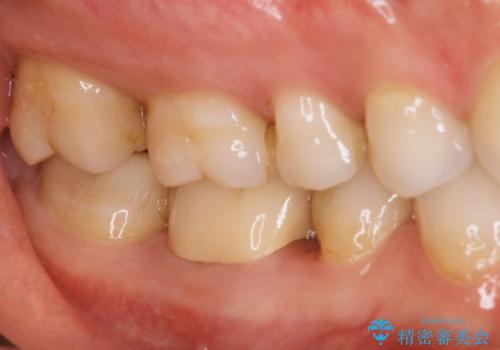

- 歯と歯の間によくものが詰まるということで来院された患者様です。

銀歯のある部分によくものが詰まるようで、診断の結果セラミックにて治療を行う計画を立てて

銀歯を外し他の歯も虫歯があったためそちらも一緒に治療を行いました。

銀歯だったところは、歯質を削る量が多かったためクラウンにて治療し、前後の歯に関してはインレーにて治療を行なっております。

また、歯肉に関してもきれいに治って患者様も満足されていました。